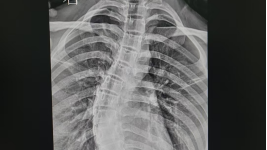

DR特色检查项目:一次曝光即可完成全脊柱成像,极大提高了脊柱疾病的检测效率,降低了患者的辐射剂量。